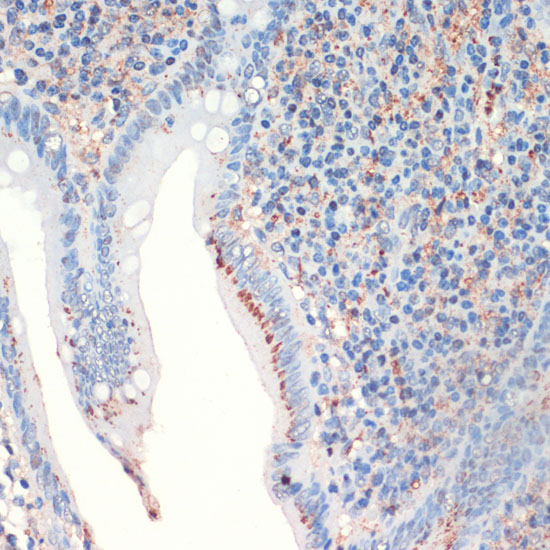

BackgroundThe hormone somatostatin has active 14 aa and 28 aa forms that are produced by alternate cleavage of the single preproprotein encoded by this gene. Somatostatin is expressed throughout the body and inhibits the release of numerous secondary hormones by binding to high-affinity G-protein-coupled somatostatin receptors. This hormone is an important regulator of the endocrine system through its interactions with pituitary growth hormone, thyroid stimulating hormone, and most hormones of the gastrointestinal tract. Somatostatin also affects rates of neurotransmission in the central nervous system and proliferation of both normal and tumorigenic cells.

ImmunogenA synthetic peptide corresponding to a sequence within amino acids 50 to the C-terminus of human SST (NP_001039.1).

ApplicationWB, IHC, IF, IP